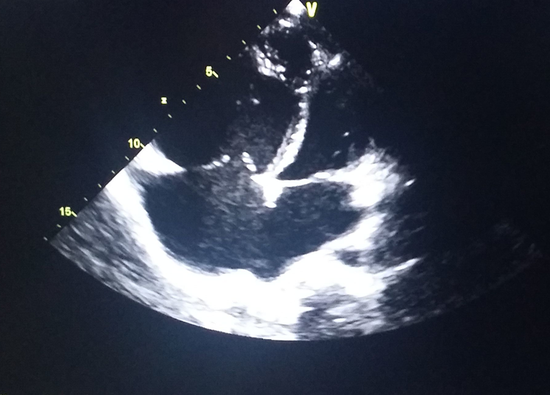

宝妈帮忙看看,是房缺还是室缺_宝宝常见病圈

306x408 - 20KB - JPEG